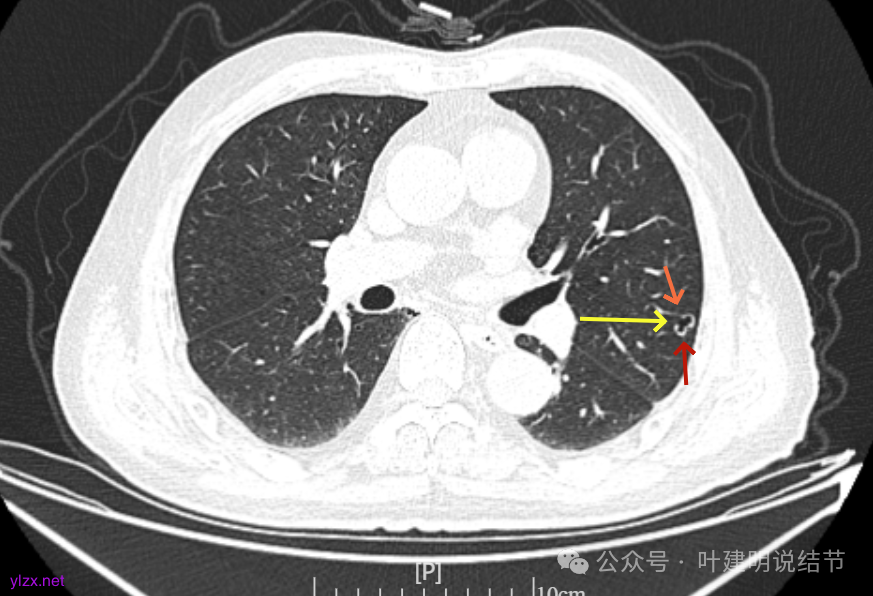

再看2023年时的影像主要层面:

左上当时也有,但囊壁明显是较现在薄的。

左肺上叶红色这处是囊腔型病灶,囊壁略不均,似有微小血管进入囊壁,对比2023年4月整个囊腔来讲有扩大,需要考虑囊腔型肺癌的可能性大。右侧蓝色的并不是典型囊腔型肺癌的表现,再加上两肺绿色这些慢支肺气肿与肺大泡的影像,右侧的就更加不确切,至少近期不能够考虑右侧也要开刀的事情。其实左侧的主病灶相对于其他表现更典型的囊腔型肺癌来说,由于囊壁密度偏高,也不是百分百必定是肺癌。我的想法还是先等脑梗情况稳定,并且间隔4~6个月复查病灶再有进展在考虑单孔胸腔镜下局部切除就可以。淋巴结可以考虑采样,但一般不至于阳性。破是不会切破的。消融不建议,囊腔灶更难通过穿刺获得病理依据,况且东西在边上,能局部楔切,当然首选手术。意见供参考!

左侧这个病灶总体上看仍是囊腔型肺癌可能性大些,但因为其两肺存在多发肺大泡的基础,而且囊壁除了结节状高密度的以外,其他的部分虽欠均匀,但差别并不太大。所以100%恶性还是难以认定的。假如没有脑梗情况,位置在边上,早点切了明确并去除病灶当然是可行的。但在反复脑梗发作的情况下,本身要神经内科情况稳定再手术较为安全,加上无法确切认定必恶性,再适当的随访也不至于影响预后。所以仍是利弊权衡与如何平衡的事情。对于这种囊腔灶,或囊肿为表现的肺癌,其实穿刺不容易阳性,针越过组织的距离并不长,其内又是空的或是液体性质的。从临床经验来看,囊腔型肺癌若囊壁是实性的,确实低分化类型的更常见些,相对风险较高些。但若是囊壁磨玻璃成分的,则也仍是贴壁为主型多见。而且从大小来讲,个人总觉得囊腔部分不能算大小,肿瘤的有形成分应该是减去空腔部分的,所以不能认定CT上测量的包括囊腔部分的来算肿瘤大小的T值。